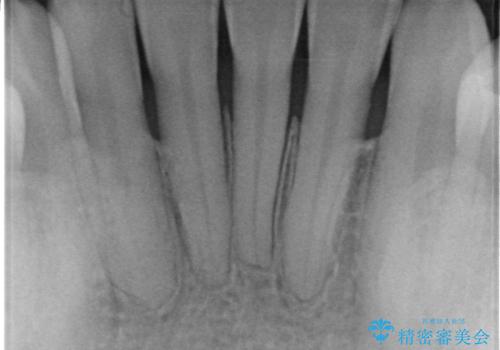

- 他院で矯正治療を終えた結果、下顎前歯の歯肉が退縮してしまい、歯根が見えていることが気になるとのことで来院された患者様です。

歯肉退縮に対して、上顎からの結合組織移植術(CTG)により、歯根の被覆を行うとともに、歯肉の厚みを増すことで将来の退縮リスクを抑制することとしました。

一度の処置で大幅に露出部の被覆に成功しましたが、更なる厚みと被覆を希望されて2回目の処置を行いました。

歯根部周辺の歯肉が非常に分厚くなり、今後の退縮リスクが大きく軽減されました。